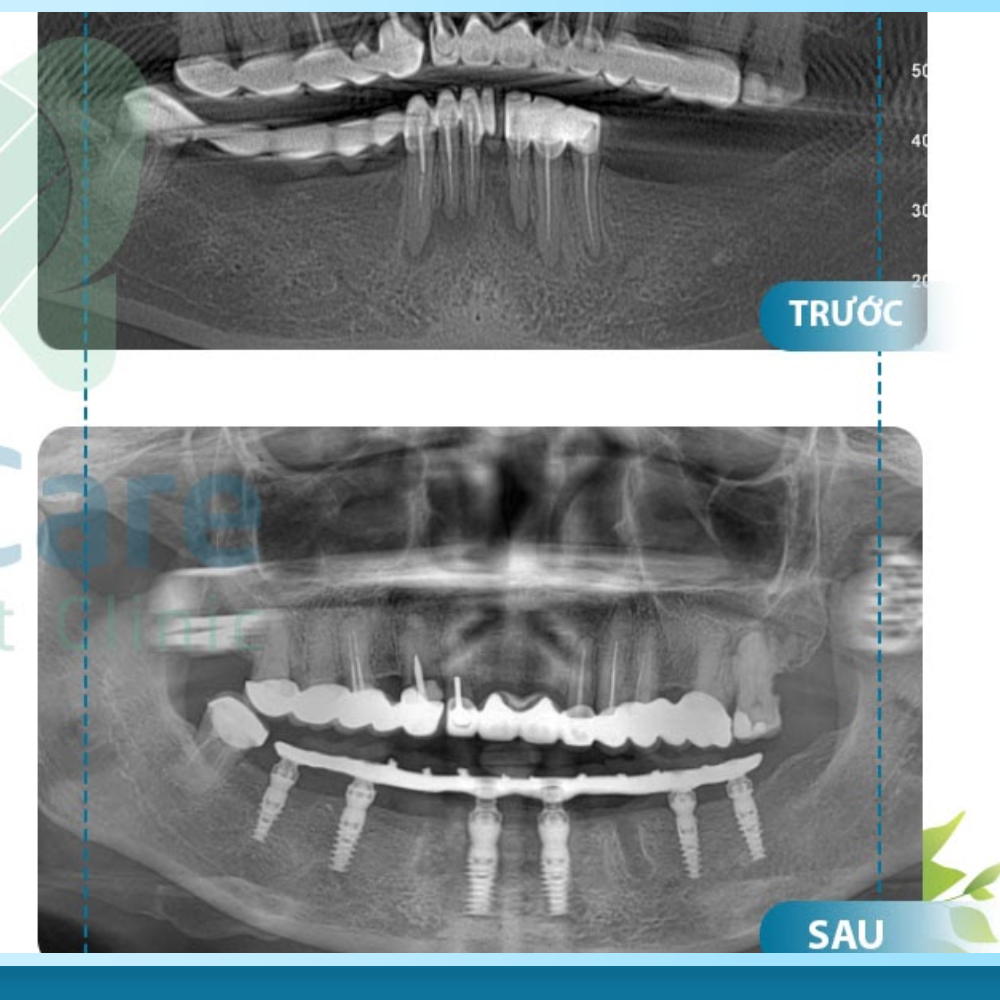

Đầu tiên là chi phí Ghép xương (Bone Grafting). Đối với những người mất răng lâu năm, xương hàm thường bị tiêu biến, trở nên mỏng và xốp. Để trụ Implant có thể đứng vững, bác sĩ buộc phải ghép thêm bột xương nhân tạo hoặc xương tự thân để tái tạo nền móng. Chi phí này thường được tính theo đơn vị răng hoặc trọng lượng (gram) bột xương sử dụng, dao động từ vài triệu đồng cho một vị trí.

Tiếp theo là chi phí Nâng xoang (Sinus Lift), một thủ thuật thường gặp khi trồng răng hàm trên. Khi mất răng, xoang hàm có xu hướng sa xuống, chiếm lấy không gian của xương. Bác sĩ cần thực hiện kỹ thuật nâng đáy xoang lên để tạo khoảng trống cho xương và trụ Implant. Tùy thuộc vào mức độ thiếu hụt mà bác sĩ sẽ chỉ định nâng xoang kín (chi phí thấp hơn) hoặc nâng xoang hở (chi phí cao hơn do kỹ thuật phức tạp).

Đi kèm với ghép xương là chi phí Màng xương (Membrane). Đây là một lớp màng sinh học (thường là Collagen) được đặt phủ lên trên bột xương ghép. Nhiệm vụ của nó là che chắn, cố định bột xương không bị trôi và ngăn mô mềm xâm lấn vào vùng ghép xương. Thông thường, chi phí màng xương sẽ được tính riêng hoặc đi kèm trong gói ghép xương tùy quy định của từng nha khoa.